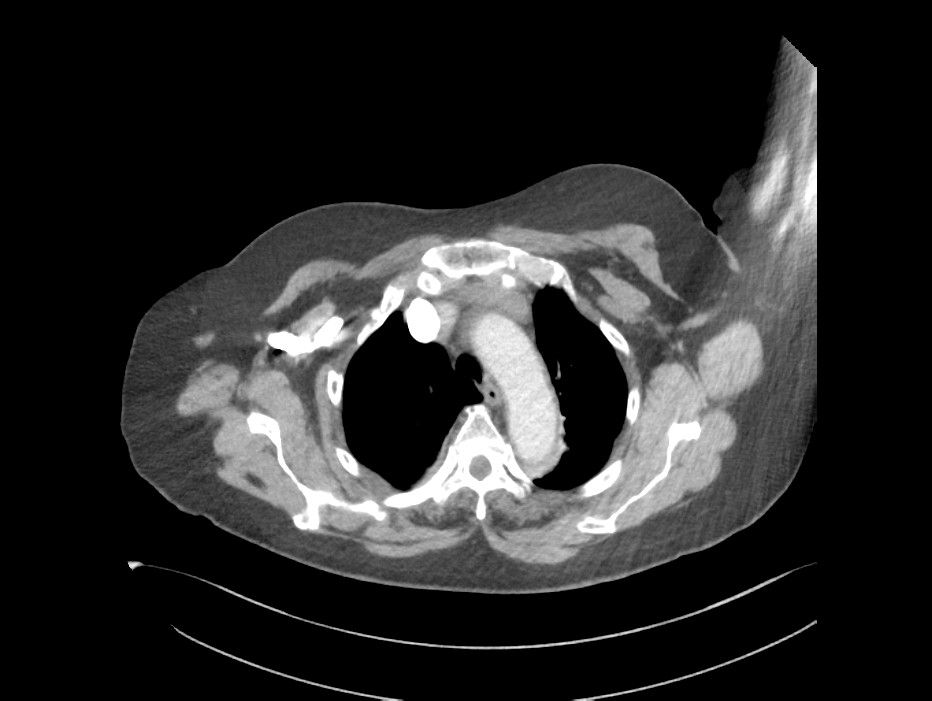

Dual Enerji İle Pulmoner Bt Anjiografi

Akciğer damar tıkanıklığı (Emboli) tanısında Bilgisayarlı Tomografi ile gerçekleştirilen Anjiografi yöntemi Standard tanı yöntemi olarak kullanılmaktadır. Bununla beraber, bu tetkik sırasında kullanılan iyot içerikli kontrast maddelerin böbreğe toksik (zararlı) olabilmesi bu tetkikin kullanılabirliğini sınırlandırmaktadır. Bu hasta grubunun genelde ileri yaşta olması ve başka sağlık sorunlarının da bulunması böbrek hasarının artmasına yol açabilmektedir.

Yeni uygulamaya girmiş olan Dual-enerji tomografi sistemleri ile çok daha düşük kontrast madde kullanılarak akciğer damar görüntülemesi (Pulmoner  Anjiografi) yapılabildiğini gösteren çalışmalar gerçekleştirilmiştir. Burada sistemin düşük enerjili X ışını kulanma özelliğinin, kullanılan kontrast madde ile sinerjik etki göstererek, kontrast maddeyi çok daha parlak göstermesi ve bu sayede kontrast madde dozajını düşürmesi özelliğine dayanmaktadır.

Sistemin bu özelliği sayesinde, Başkent Üniversitesi Adana Hastanesi bünyesindeki yeni versiyon Dual-Enerji bilgisayarlı tomografi cihazında da normalde diğer merkezlerde kullanılan kontrast maddenin yaklaşık 1/3 miktarı ile son derece başarılı Akciğer damar görüntülemesi (Pulmoner  Anjiografi) ve aynı seansta akciğerlerin kanlanma düzeyini gösteren “Perfüzyon” değerlendirmesi de yapılabilmektedir. Bu sayede merkezimizde, başta böbrek sorunu olan hastalar olmak üzere birçok hasta grubunun kontrast madde kaynaklı böbrek hasarı (nefrotoksisite) olmadan akciğer damar yatağı (Pulmoner  Anjiografi) görüntülemesi yapılabilmektedir.